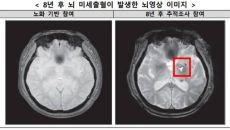

수면무호흡증 중등도 이상이면 뇌 미세출혈 위험 2배 커져

중등도 이상 수면무호흡증, 뇌 미세출혈 위험 2배 ↑

중등도 이상의 수면 무호흡이 정상 수면 시보다 뇌 미세출혈의 위험을 두배 이상 높이는 것으로 나타났다. 질병관리청 국립보건연구- 2025.12.03 12:00